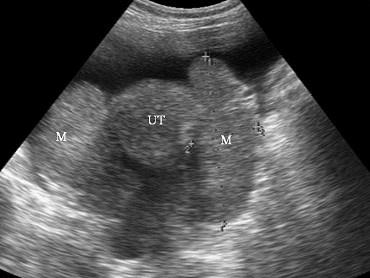

问题 女性,49岁,胃部不适、消瘦3个月就诊。超声检查如图,最可能的诊断是 ( )

选项 A、卵巢转移癌 B、正常声像图 C、卵巢纤维瘤 D、炎性包块 E、畸胎瘤

答案 A